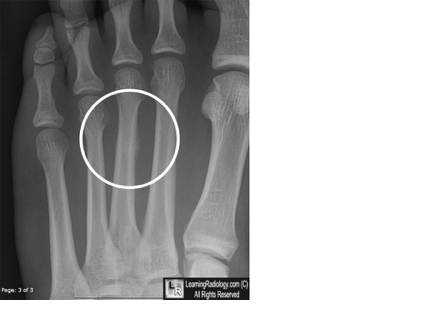

A metatarsal stress fracture is an injury that involves tiny cracks in the bone.